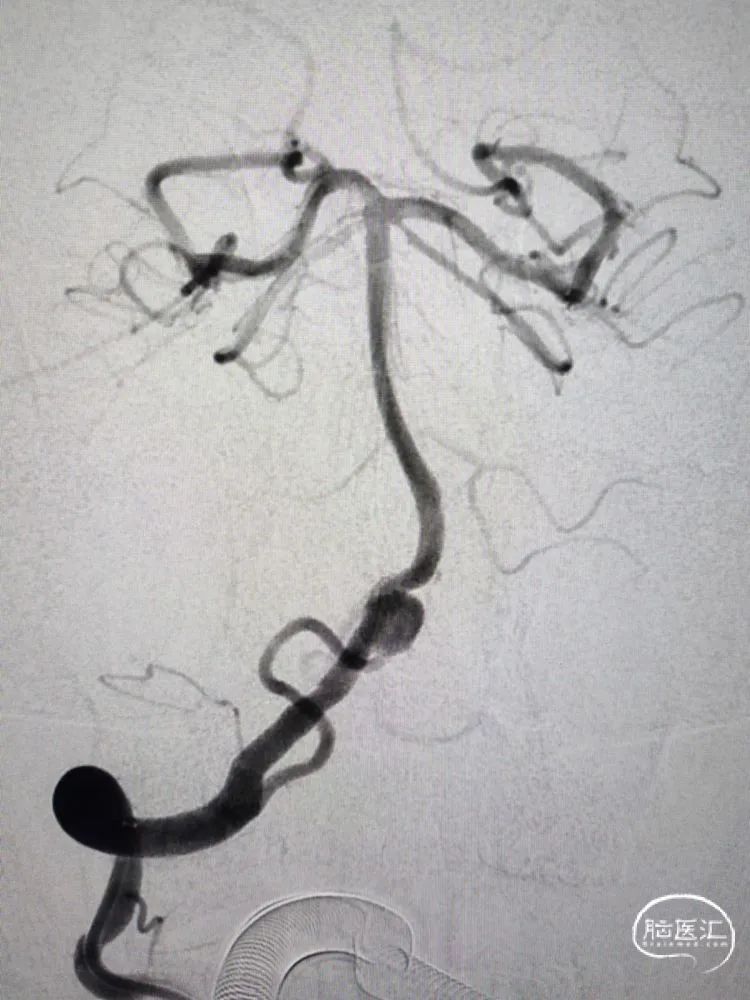

改进版的Tubridge血流导向密网支架到位后,支架在远端预打开再回撤定位,从双椎动脉汇合处下方开始释放,缓慢推出支架进行头端锚定,改进版的Tubridge血流导向密网支架有效改善了头端打开和锚定性能,支架远端刚好落在汇合处下方,造影观察支架充分锚定后,继续缓慢释放支架至瘤颈中段,造影确认后,随后等张释放支架完毕,支架完全覆盖动脉瘤。改进版的Tubridge血流导向密网支架优化了编织丝和编织密度,支架支撑力显著提升,支架打开效果优异,全段充分张开贴壁。

正侧位造影以及三维重建提示动脉瘤瘤囊充盈略减缓,晚期可见造影剂滞留,支架全段完全张开贴壁,载瘤动脉血流通畅良好。